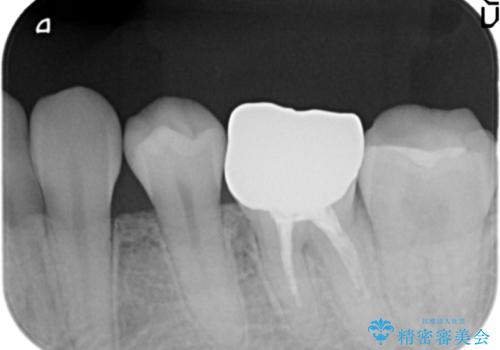

- 笑った時に目立つ、下の歯の銀歯をセラミックにしたいと来院されました。

症状・病変はなかったため根管治療は行わず、クラウンのやりかえのみの治療計画としました。